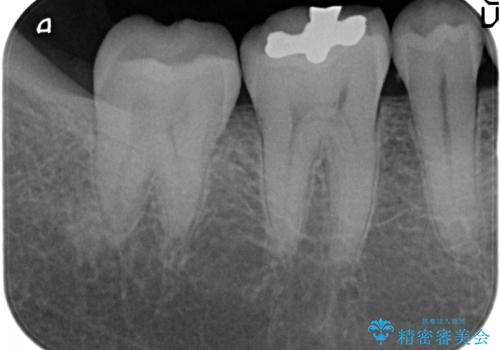

- 右下の一番奥の歯で冷たいものを飲むとしみるので診て欲しいといらっしゃった方の症例です。

ついでに銀歯もやり替えたいとのことだったので、右下6、7番目の歯に対してセラミックインレーによる修復を行いました。